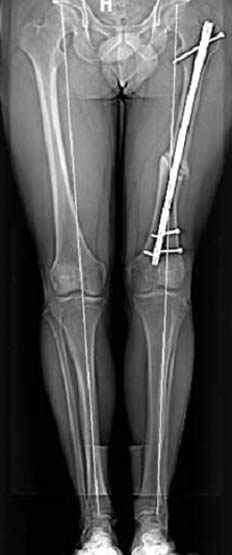

Интересно бы посмотреть рентгенограмму таза (оба сустава) а также рентгенгорамму с захватом коленных суставов (по Dror Paley).

Отправитель: Djoldas Kuldjanov 23 Ноябрь 2004, 18:21

пластическая модель; и коррекция бедра аппаратом Илизарова.

Имею другие снимки тоже, получится как отчет о моей работе.